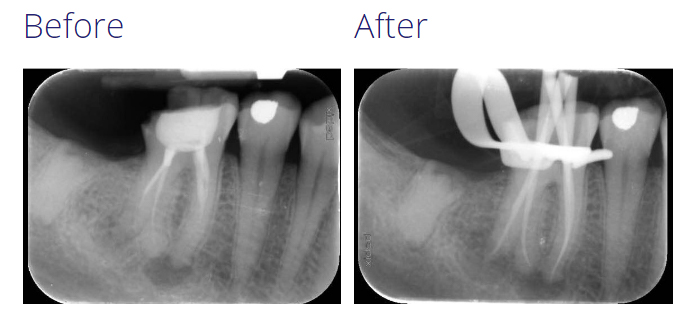

This case demonstrates the management of chronic apical periodontitis associated with a failing root canal treatment.

The tooth was of strategic importance to the patient as it was the last standing molar in that quadrant.

Root canal pretreatment was carried out over two visits with an inter-appointment dressing of calcium hydroxide. This has been shown to reduce the bacterial load within root canals more than irrigation alone.

A good prognostic factor in root canal pretreatments is the ability to reach working length in all the canals, this is usually possible if the original anatomy has been respected during the primary treatment (i.e. no ledges or transportations).

The final result was satisfactory and the resulting prognosis was good.

A 12 month review revealed complete healing of the apical radiolucencies associated with the tooth.